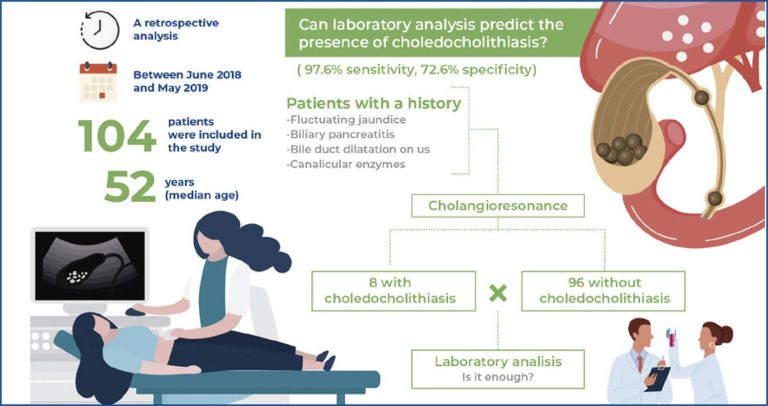

Highlights Alkaline phosphatase: sensitivity of 97.6% and specificity of 72.6% for choledocholitiasis. The average cost of cholangioresonance would have decreased by almost half for each patient in this study. ABSTRACT Objective To assess the predictive value of preoperative serum laboratory test results for identifying choledocholithiasis and reduce the use of cholangioresonance and its inherent costs. Methods Patients aged 21-69 years who underwent preoperative cholangioresonance examination at our institute were included. Patients with a history of fluctuating jaundice or biliary pancreatitis, […]